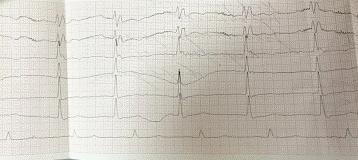

ЭКГ:

Ритм правильный синусовый

ЧСС 79 уд/мин

Положение электрической оси сердца: срединное

Продолжительность Р: 0,12

Продолжительность РQ: 0,18

Продолжительность QRS: 1,35

Заключение: Гипертрофия левого желудочка, БПНПГ, нарушение процессов деполяризации передней стенки, верхушки сердца.